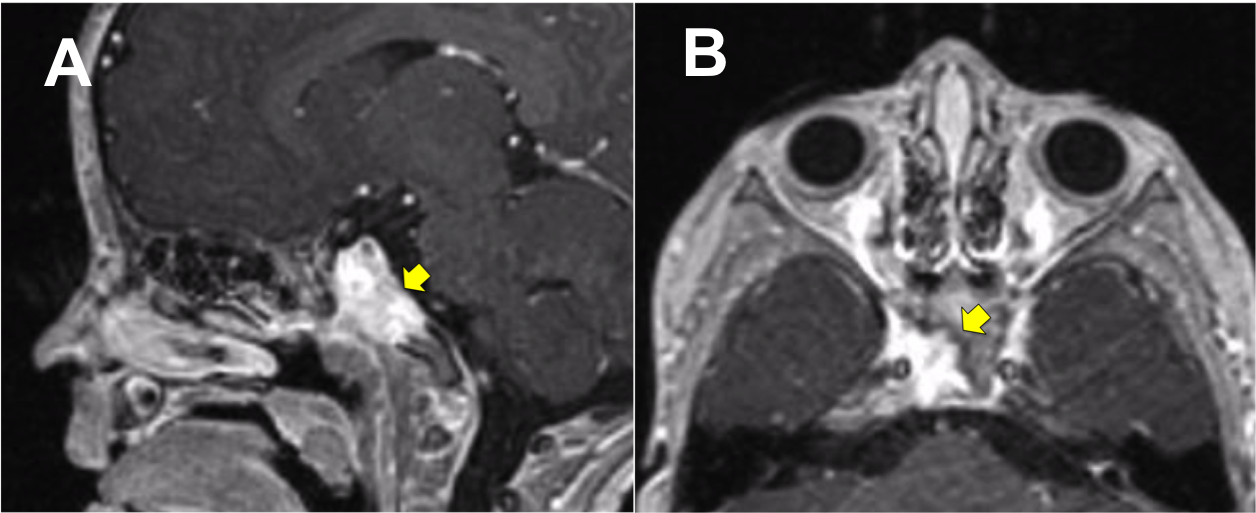

Introducción: La cirugía endoscópica endonasal se ha convertido en una herramienta fundamental para el manejo de patologías que comprometen la base de cráneo. En casos bien seleccionados, estas técnicas permiten resecciones quirúrgicas con una menor morbilidad sin comprometer los principios oncológicos de resección. Con el desarrollo de instrumental especializado, nuevas tecnologías y la experiencia de los cirujanos, la cirugía endoscópica endonasal se usa cada vez más en cirugía de base de cráneo en niños.

Objetivo: presentar una serie de casos de pacientes pediátricos con tumores de base de cráneo manejados con cirugía endoscópica endonasal.

Diseño: Estudio observacional descriptivo de tipo serie de casos. Metodología: se describe la experiencia con pacientes pediátricos llevados a cirugía endoscópica endonasal para manejo de tumores de base de cráneo en el Instituto Nacional de Cancerología entre julio de 2014 y diciembre de 2016.

Resultados: Fueron intervenidos 8 pacientes entre los 2 y 14 años, con una edad promedio de nueve años y un seguimiento promedio de 16 meses. En el 75% se hizo una resección total del tumor. Un paciente requirió una reintervención y un paciente fue sometido a radiocirugía post-operatoria. 1 paciente falleció a pesar de múltiples intervenciones, quimioterapia y radioterapia.

Conclusión: La cirugía endoscópica endonasal para tumores de base de cráneo puede ser utilizada de forma segura en los pacientes pediátricos, es una técnica que en casos bien seleccionados pueden ofrecer excelentes resultados disminuyendo la morbilidad y complicaciones de las técnicas abiertas.